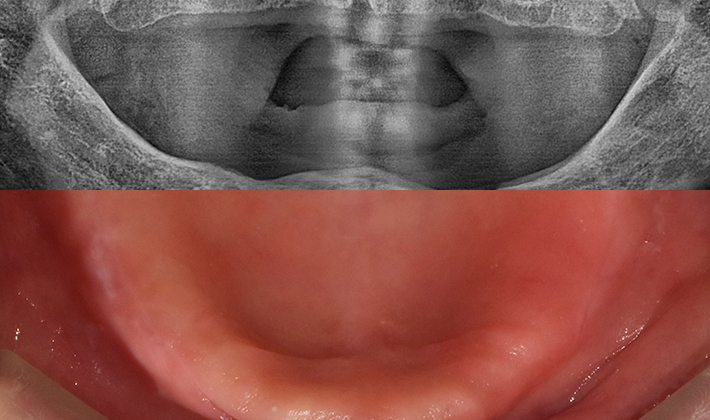

5060 시니어 임플란트

건강하고 오래가는 시니어 임플란트,

치료 사례부터 남다릅니다.

before

after

※ 위 임상사진은 동일조건으로 촬영되었으며, 사진에 대한 별도의 조작이 처리되지 않았습니다.

※ 위 임상사진 및 포트레이트는 환자와의 포괄적인 초상권 계약 이후 사용하고 있습니다.

※ 수술 및 치료과정에서 부작용이 발생할 수 있으므로 충분한 상담과 신중한 판단이 요구됩니다.